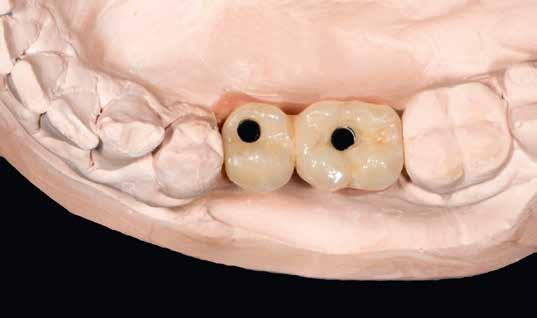

A digitális lenyomatvételt (4. kép) követően a primer részek előállításához a CAD szoftverben vágatlan fogívet szegmensekre osztottuk, és a pontosság ellenőrzésére csonkokat generáltunk (5-6. képek). Az ebből nyert STL-adatállományt virtuálisan illesztettük a 3D nyomtató építőasztalára (7. kép), és a Bego cég VarseoWax Model segítségével Anycubic Photon Mono X LCD-nyomtatóval kinyomtattuk a mintákat (8. kép)

Primerkorona tervezés

A 0°-os, egymással szemben legalább két 3 mm-es magasságú felületet felmutató primer koronákat ismét a CAD szoftverrel terveztük meg (9. kép). A gyártás a Bego CAD/ CAM gyártóközpontjában, Brémában, SLM-eljárással történt, Wirobond C+ (Bego) ötvözetből.

Egyéni kanál

A mesterminta készítéséhez szükség volt hagyományos lenyomatra is, mert nincs gyakorlati megoldás a primer koronák szájbéli pozíciójának intraorális szkenneléssel történő digitális rögzítésére. Ehhez egyéni kanalat készítettünk. Lemásoltuk a CAD-konstrukció adatállományát, és illesztettük a preparációs szkennelést. Ezzel további beolvasást tettünk feleslegessé, nem kellett megvárnunk a primerek elkészültét.

A minta darabolása nem volt lehetséges. Mivel a nyomtatás nem szükséges, el is hanyagoltuk (10. kép)

A lenyomatkanál (11. kép) Varseo S DLP-nyomtatóval készült, VarseoWax Tray (Bego) anyagból, nyomtatva (12. kép)

A közben megérkezett primer koronák a minta csonkjaira voltak passzíthatók (13. kép)